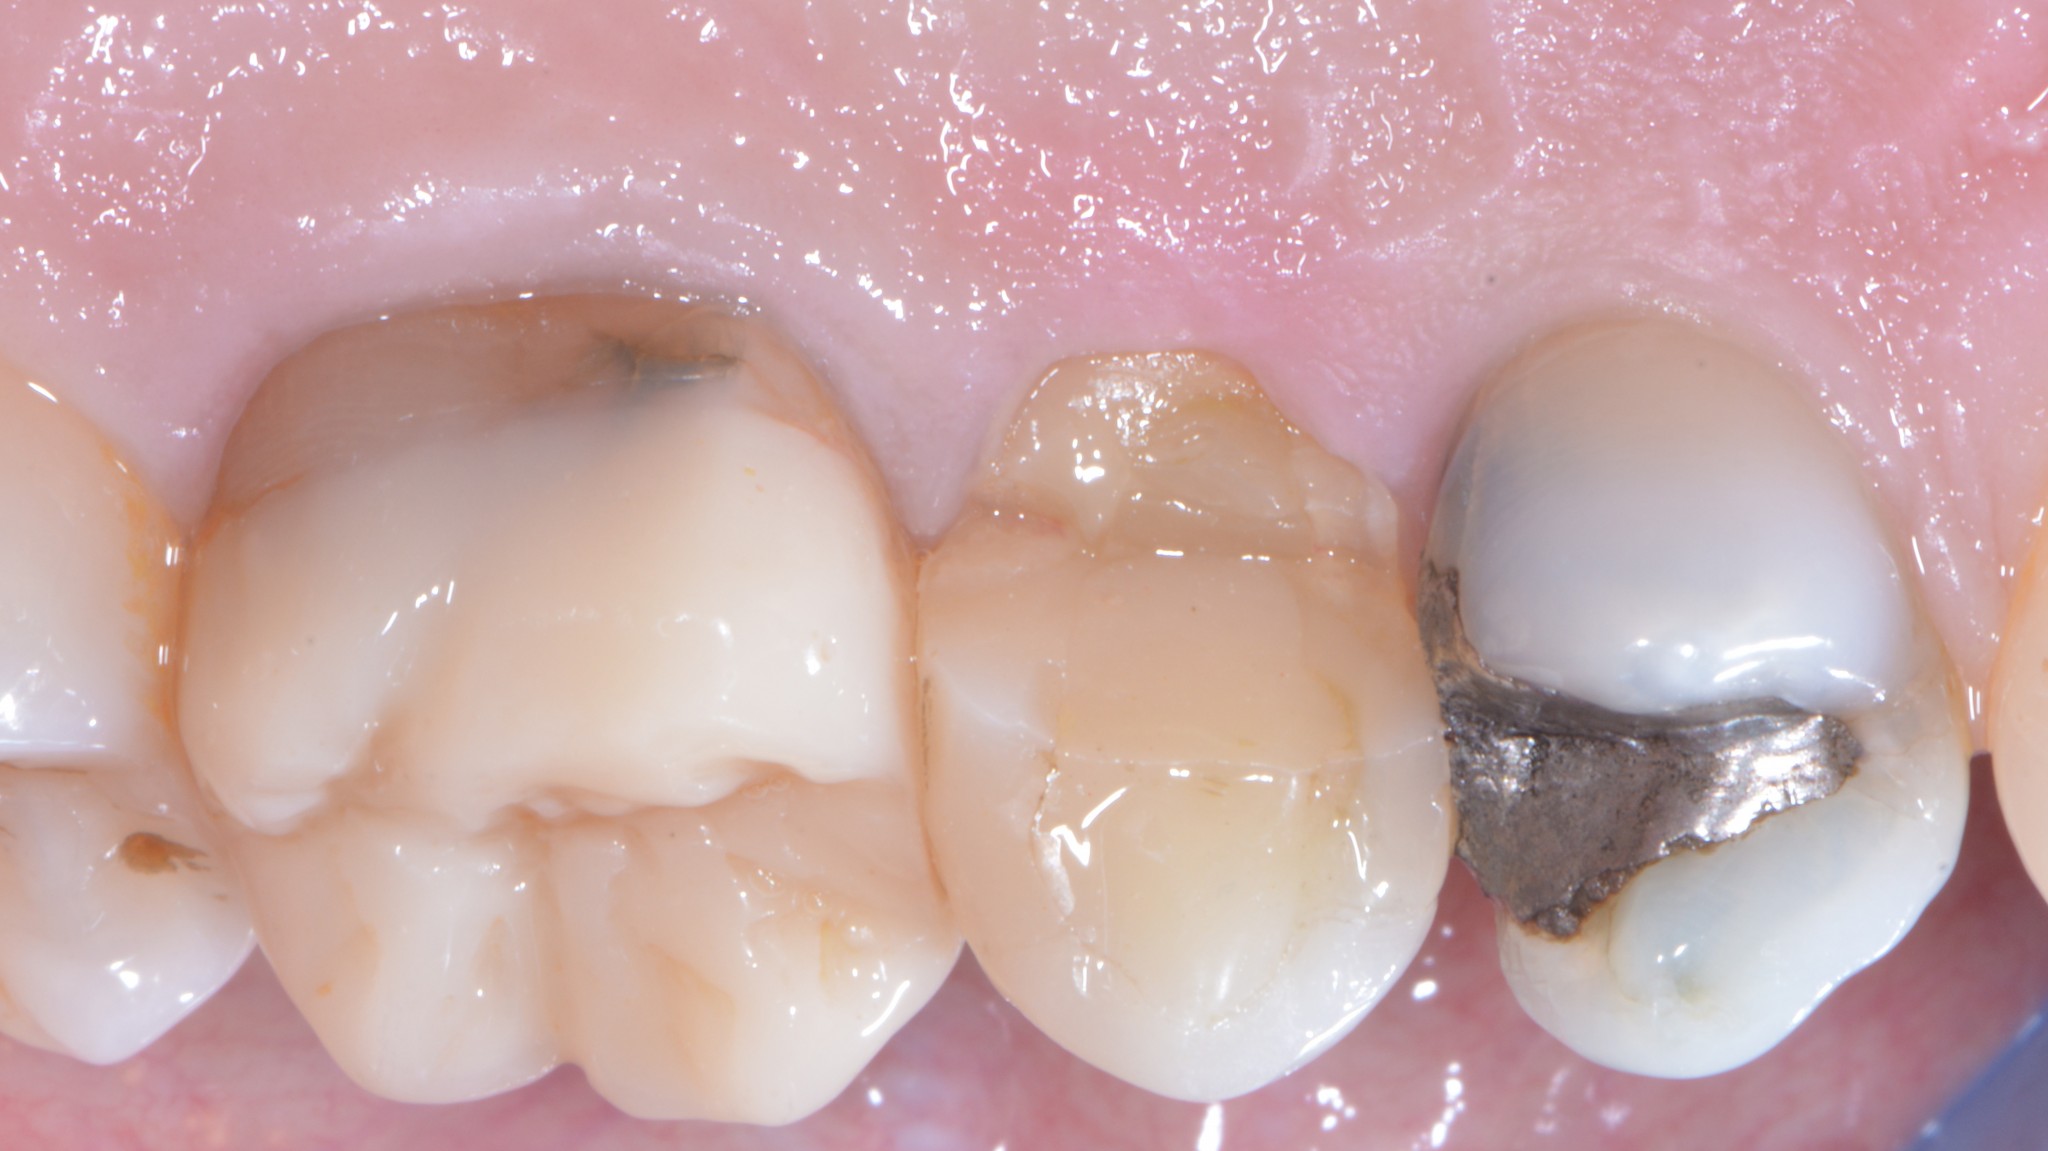

Ecco cosa succede:

Frattura coronale complicata con margine di frattura sottogengivale di almeno tre millimetri.

Spesso capita che i premolari e i molari superiori si fratturino dal lato palatino. In questi casi possiamo eseguire un allungamento che si limita a quell’aspetto in modo da preservare l’estetica vestibolare pur mantenendo l’imprescindibile condizione di un’anatomia positiva della festonatura gengivale.